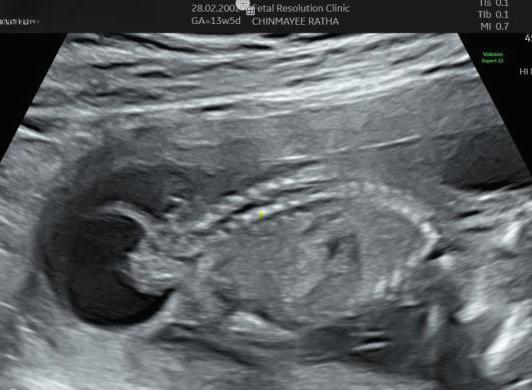

The first trimester— spanning from conception to 13+6 weeks—is no longer considered a “blind phase” of pregnancy. With the evolution of highresolution ultrasound, color Doppler and advanced biochemical screening, this period has transformed into a window of opportunity for early fetal evaluation, risk prediction and preventive strategies.

First-trimester fetal evaluation is not limited to dating the pregnancy or confirming viability—it is the foundation of predictive, preventive, and personalized obstetric care.

1. EARLY PREGNANCY SCAN (6–10 WEEKS)

Indications:

1. Confirmation of pregnancy.

2. location of pregnancy.

3. Number of fetus.

4. Cardiac activity.

5. Initial dating.

6. Assessment of uterine contour to ruleout any uterine anamolies.

7. Examnation of adenexa.

Findings:

• Gestational sac at ~4.5–5 weeks-Appears as anechoic fluid filled structure surrounded by a decidual reaction (Double Decidual sac sign).

• Measure Mean sac diameter .

• Yolk sac appear around ~5–5.5 weeks.

• Embryo with cardiac activity around 6 weeks.